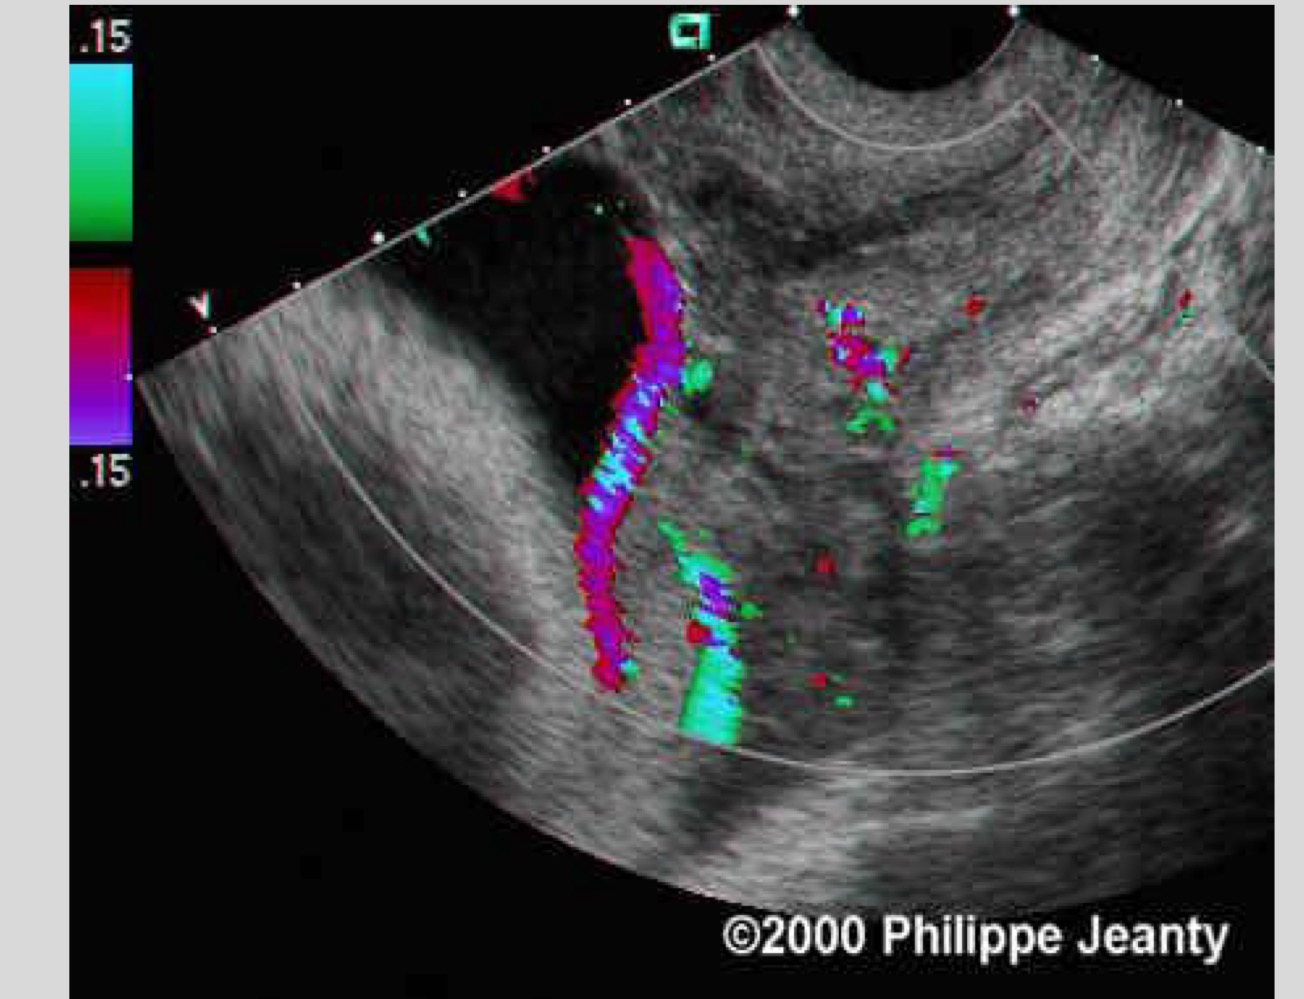

How is vasa previa best diagnosed

Transvaginal ultrasound with color Doppler

What is the role of color Doppler in vasa previa

To visualize fetal vessels near the cervix